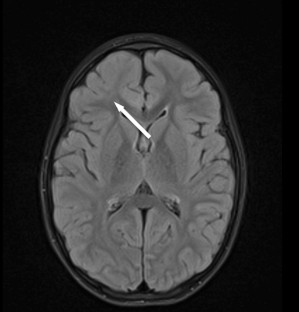

Lennox–Gastaut syndrome (LGS) is a rare, age-related syndrome, characterized by multiple seizure types, mental regression, and specific EEG abnormalities. It is one of the most challenging epilepsy: treatment is rarely effective and the final prognosis remains poor, despite the availability of several antiepileptic drugs, validated through well-designed, randomized, controlled trials. However, it is reasonable to consider non-medical treatments, such as surgery, after failure of two-to-three drugs. This review has as goal to describe systematically the different therapeutic options for LGS, including, not only recognized antiepileptic drugs, but also new oral drugs, immune therapy, diet, surgery, and neurostimulation techniques.